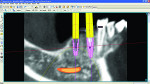

A cone-beam computed tomography (CBCT) scan was conducted and reformatted by 3D Diagnostics (www.3ddx.com) so that the implants’ placement could be planned with SimPlant® (Materialise Dental, www.materialisedental.com). The treatment modality selected was constructed so that the treatment would begin with three maxillary implants with a fixed bridge for the upper left quadrant and two implants in the No. 20 and No. 21 sites, which would be joined to future mandibular implants to fabricate a hybrid prosthesis or mandibular fixed implant bridge. The proper consent was received and the implants were placed during the first surgery.

The reformatting done by 3DDX allowed virtual placement of the implants and measurements from the existing teeth and roots to be used for pilot osteotomy placement. The loss of tooth No. 10 after initial treatment planning led to a decision to place implant No. 11 at a mesial angle so that the antero-posterior distance of the bridge could be optimized.

The implant planning for the initial implant placement was viewed in the SimPlant planner (Figure 6 though Figure 10) and MIS’s SEVEN® implants (www.mis-implants.com) were chosen for placement due to their cost effectiveness; sand-blasted and acid-etched surface, which increased the surface area; sterile single final drill; and implant stability at placement. The placement of five additional implants post-edentulation and mandibular ridge leveling can be seen in the SimPlant full window view. The SimPlant treatment plan was designed to address the edge to edge anterior bite. This would be done by performing an osteoplasty of the mandibular anterior and placing the implants in a more uprighted position with respect to the existing mandibular dentition. Placement of implants inferiorly and lingually would allow for a modification from a splayed Class III to a Class I occlusal relationship. The removal of the anterior teeth combined with osteoplasty and implant placement in a more inferior position would allow for maintaining her existing vertical dimension of occlusion. The patient agreed to the cost and number of implants, but she was given the option to leave the remaining lower teeth and place smaller-diameter implants in the posterior regions, so a treatment variation was created for this scenario as well. She wasn’t certain whether she could approve full mandibular edentulation until she evaluated the initial procedure’s success. Lastly, the maxillary full-arch treatment was planned to facilitate phase 2 treatment and provide her with an upgrade path.7